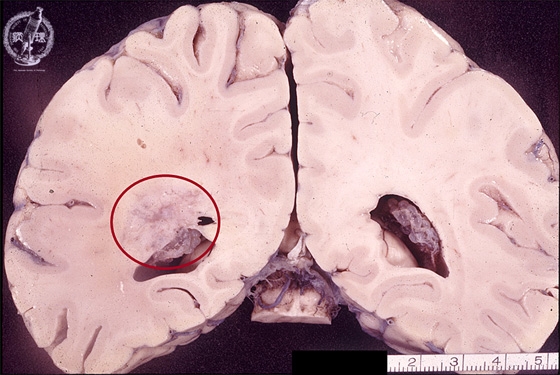

- ★(8)Glioma(Astrocytoma)

Macroscopic findings: Relatively indistinct tumor mass was detected in the lateral lobe around the left lateral ventricle (red circle).